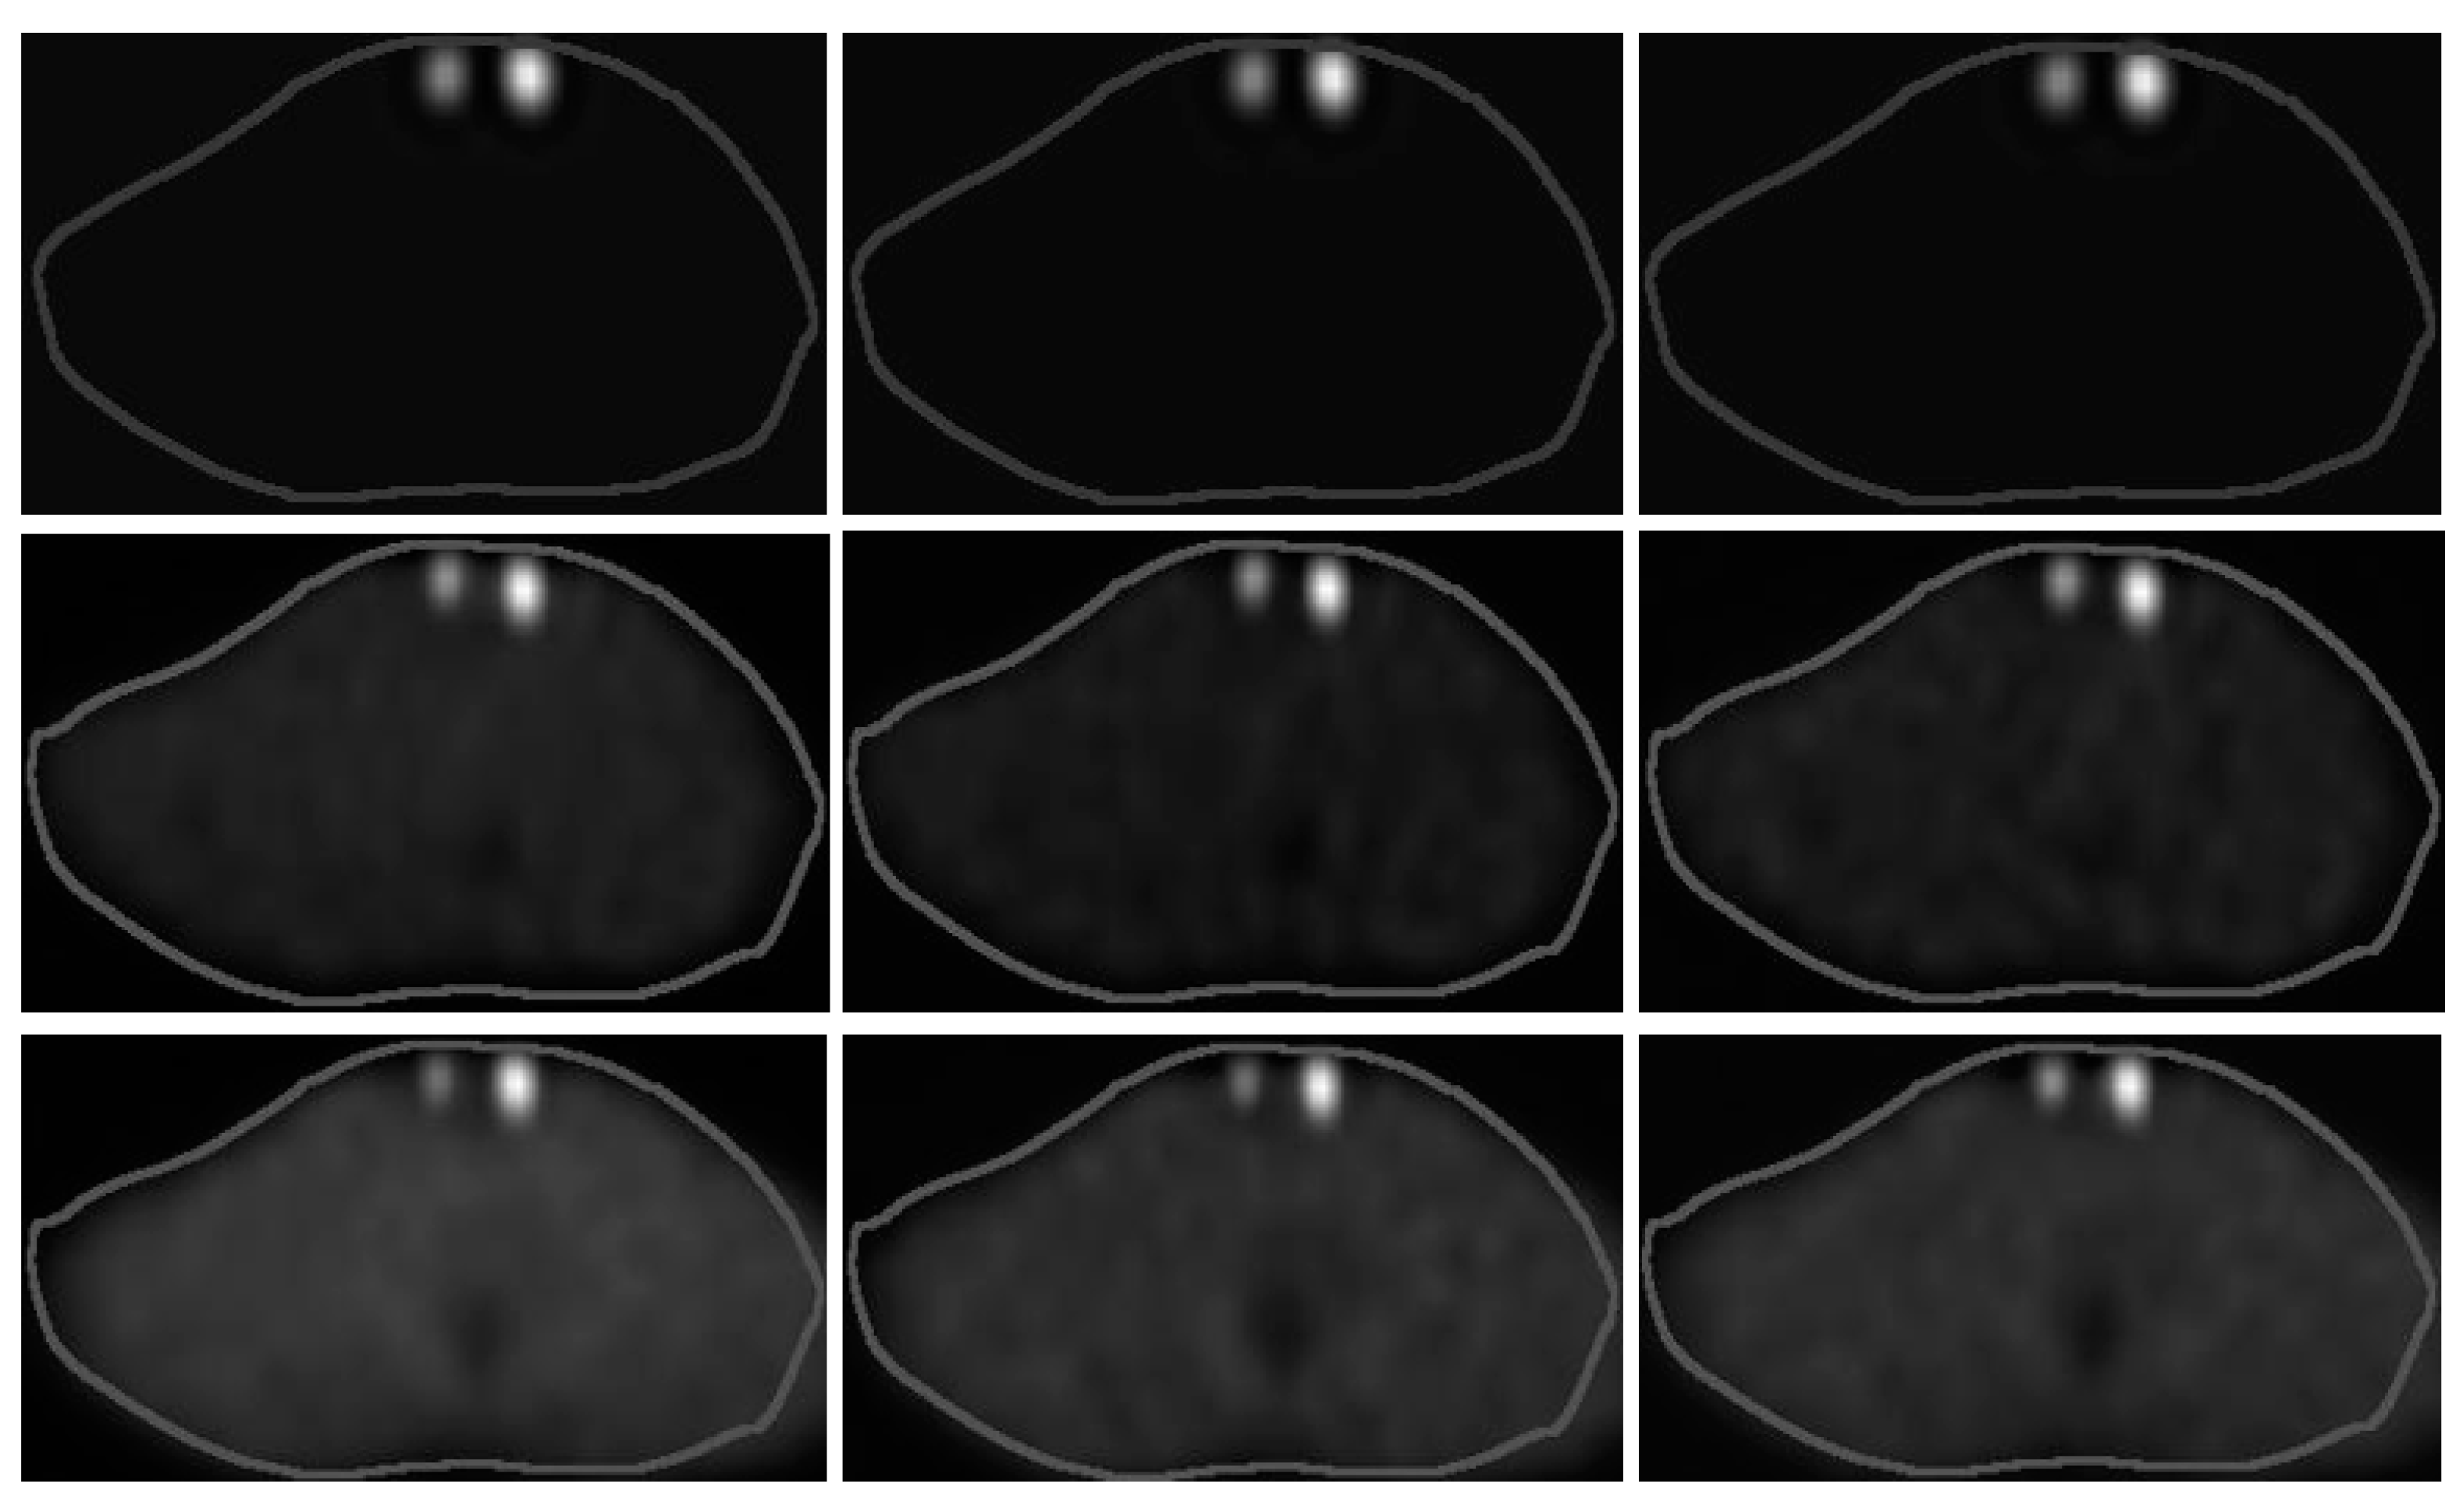

Figure 7 shows the NSC, DEW and TEW scatter-corrected SPECT/CT images without and with an Rbkg of 5% and 10%. Very similar activities per mL were administered within the 1.5 and 3 mL remnants. The physicians reported that they could not distinguish significant differences among the images without background activity. However, they reported that the image contrast for both remnants was improved at an Rbkg of 10% compared to an Rbkg of 5% when applying the TEW SC technique, and thus, they were more confident in assessing the volume difference between the two remnants.

Figure 7.

(Left column) NSC, (middle column) DEW and (right column) TEW scatter-corrected SPECT/CT images without (top row) and with an Rbkg of (middle row) 5% and (bottom row) 10%. Table 1 (acquisitions 1, 8, 9) presents the administered activities within the 1.5 (left side of each slice) and 3 mL (right side of each slice) remnants.